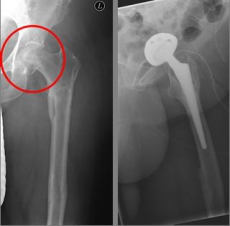

Oberschenkel 3

Picture: This picture shows the treatment of a severely displaced fracture with a so-called duo head prosthesis. The acetabulum was left here.

Oberschenkel 4

Picture: In this case, there was already a wear of the hip joint and the affected patient was relatively young, so that a cement-free total endoprosthesis (TEP) of the hip was selected for the treatment of the femoral neck fracture. Here, in addition to the femoral head, the acetabular cup was replaced by an implant.